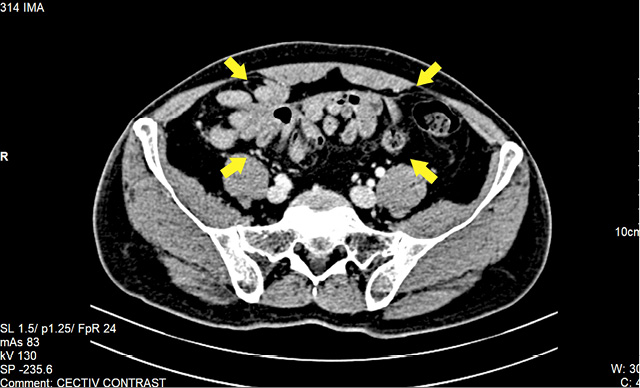

We present a case of a 62-year-old man who presented to the surgical emergency department with complaints of distension of the abdomen and inability to pass stool or gas for 48 hours. He also had three episodes of bilious vomiting. On clinical examination, there was tachycardia and signs of dehydration. The abdomen was distended with absent bowel sounds. He was admitted and started on parenteral intravenous fluid resuscitation. All investigations including hematology and biochemistry were normal. Chest radiograph with both domes of the diaphragm was normal. An abdominal radiograph revealed multiple air-fluid levels suggestive of small bowel obstruction. A contrast-enhanced CT scan of the abdomen revealed dilatation of proximal ileal and jejunal loops with abruptly cut off at the level of the proximal-mid ileal loop. There was circumferential thickening of proximal-mid ileal loops. There was twisting of distal jejunal and proximal ileal loops along with a defect in the mesentery at the level of umbilicus likely to be a small bowel trans mesenteric internal hernia (Figures 1, 2). Abdominal Tuberculosis workup was done with Polymerase Chain Reaction (PCR) for mycobacterium, manteaux test and Cartridge Based Nucleic Acid Amplification Test (CB-NAAT) Sputum were negative. He was managed conservatively with nasogastric decompression with a nasogastric tube, intravenous fluids, and symptomatic drugs. There was partial relief of obstruction after the second day of admission.

Clinical diagnosis is difficult because of non-specific symptoms. Plain radiographs of the abdomen may reveal nonspecific bowel loop dilatation and air-fluid levels. Ultrasound abdomen may reveal a cauliflower or a trilaminar appearance of the bowel. CT has facilitated accurate preoperative diagnosis, long before the patient presents with full-fledged symptoms of acute intestinal obstruction. CT scan is the imaging of choice and plays a significant role in excluding the secondary causes and helps in patient management. The identification of thickened contrast-enhanced peritoneal membrane with encapsulated bowel loops called “cauliflower sign” is a significant finding. CT also helps in identifying the cause and delineating the complications [4–6].